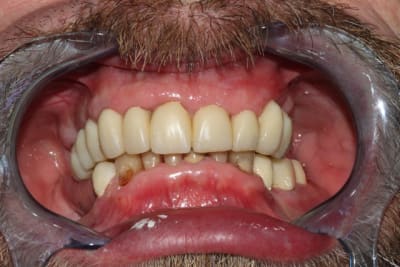

Du coup, pour finir:

-En janvier, c'est reparti: reprise de traitement 12 13 14. Comme je le disais, les RCR 15 16 sont en bon état, les endos asyptomatiques même si pas parfaites: je n'y ai pas touché, l'avenir me dira si j'ai eu raison.

Inlays-core 12 13 14, j'aurais pu réaliser des RCRs mais je ne me sentais pas de paralléliser les 9 piliers à l'oeil.

Puis classique essayage d'armature (parfaite, merci le labo), et pose. Réglages occlusaux le lendemain.

Photos de l'occlusion avant les réglages occlusaux, tout juste sorti du labo. J'ai diminué les contacts sur la 23 en entrée de cycle, et sur la 21 en incision. (bleu en statique, rouge en cycles masticatoires)

Pose des implants prévue pour cet été, donc couronnes vers Noël probablement.

Je peaufinerai probablement encore un peu l'occlusion dans 6 mois, lorsqu'on posera 45 46.